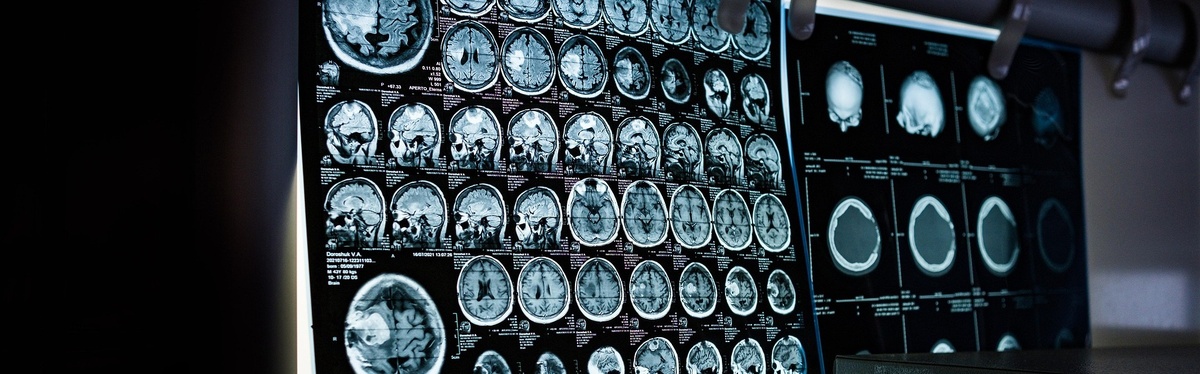

Вы когда-нибудь слышали о способности мозга адаптироваться и меняться в ответ на новый опыт, обучение и повреждение. Этот динамический процесс позволяет нашим нейронным связям перестраиваться таким образом, что это может привести к улучшению когнитивных функций и даже восстановлению способностей, утраченных в результате повреждения!

Нейропластичность — термин, описывающий способность мозга трансформировать свою структуру и функции.

Нейропластичность мозга не только позволяет приобретать новые навыки, но и играет ключевую роль в адаптации к изменениям и восстановлении после травм.